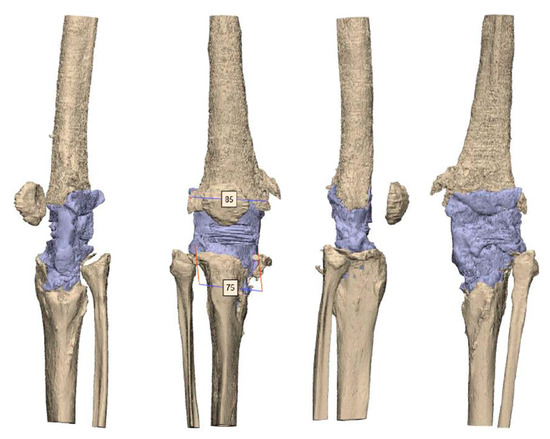

2.3. Manufacturing

2.4. Planning and Surgical Technique